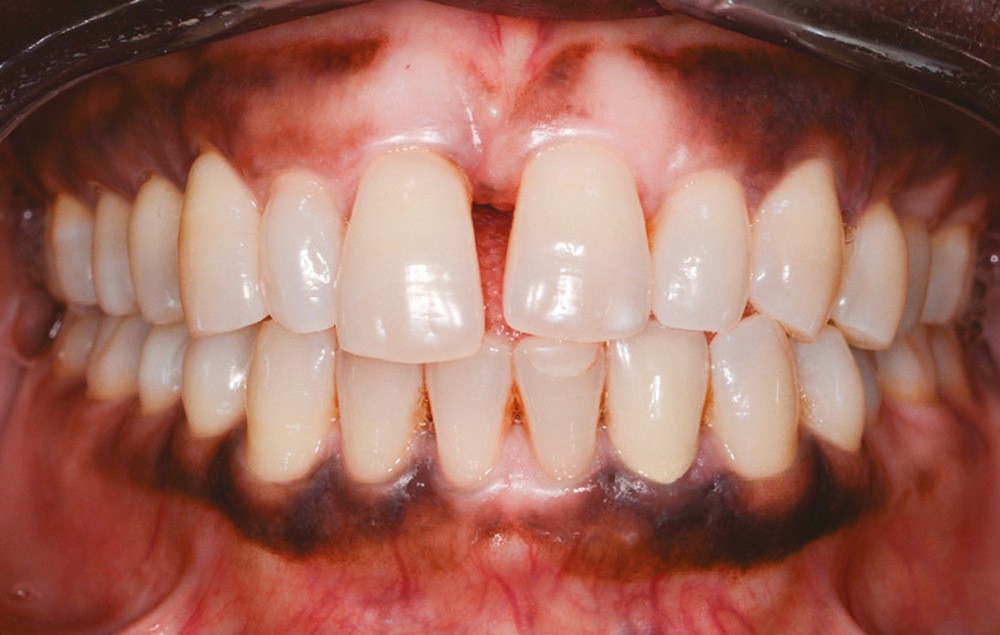

Une femme âgée de 33 ans, sans antécédents médico-chirurgicaux notables, consulte pour la correction de l’égression de son incisive centrale qu’elle juge disgracieuse dans le sourire (fig. 1).

L’observation clinique après traitement parodontal initial révèle, au niveau interarcade, des rapports de classe I molaire bilatéraux associés à des rapports de bout à bout incisif. Dans la dimension verticale, elle présente une légère infraclusion antérieure. On ne note pas d’anomalie de la dimension transversale (fig. 3 à 5). À l’examen intra-arcade, on constate des diastèmes maxillaires interincisifs (1 mm), en distal de 13 (0,5 mm) et de 24 (1 mm) ainsi que des malpositions unitaires (linguoversion de 12, rotation mésio-vestibulaire disto-linguale de 24). À la mandibule, on observe une couronne céramométallique au niveau de 32 plus large de 1,5 mm que les autres incisives ainsi qu’une rotation mésio- linguale de 35 (fig. 6 à 8). En diduction, on note une interférence au niveau de 24.